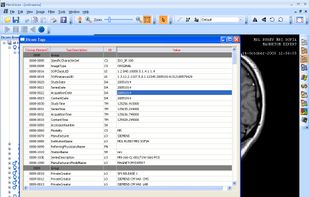

MicroDicom is an application for primary processing and preservation of medical images in DICOM format